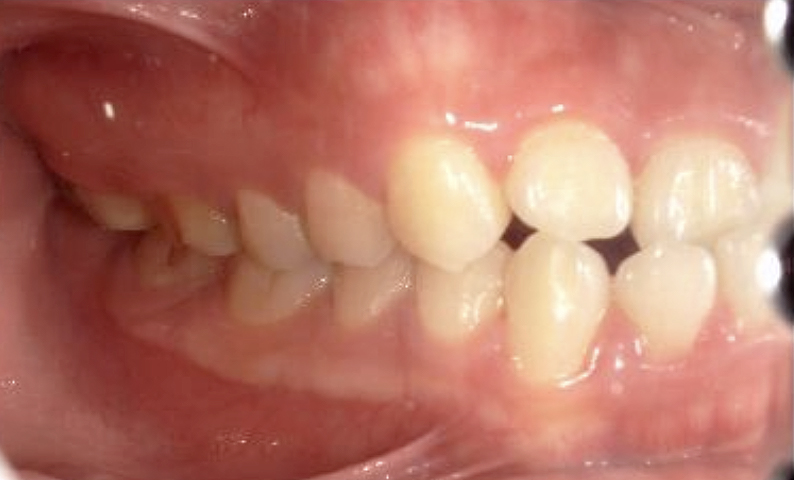

症例_022 上下顎の部分矯正

治療期間:7ヶ月金額:54万円+税女性前歯のガタガタ八重歯一部反対咬合

| Before | After |